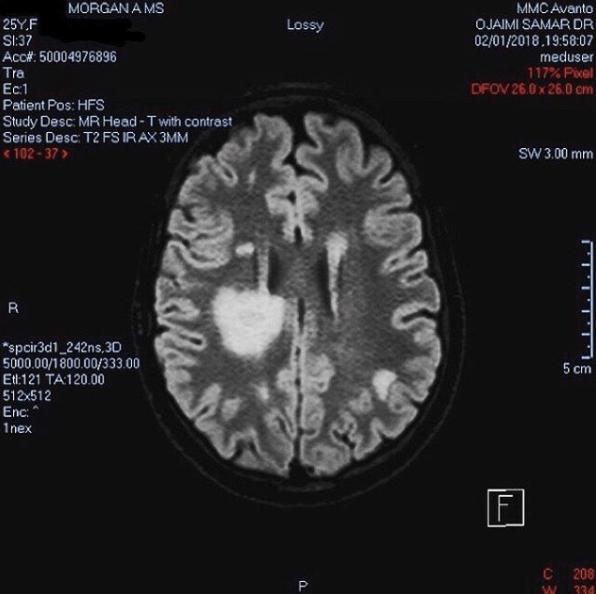

Long story short, I had my annual brain MRI brought forward, and after a few multi-disciplinary panels and discussions between dermatology, oncology, radiology, immunology and neurology, they THINK that what they can see on the scans is just my MS/interstitial lung disease.

In any case, there was a lot of debate about my brain because I have so many new lesions that weren’t present on my last MRI. We know my old lesions are lesions and not tumours because we have been watching them grow/shrink over time. It’s not a surprise I’ve developed new lesions because I stopped MS disease modifying therapy in June last year after it literally nearly killed me, but what I was unprepared for is how big the new lesions are. It’s a shock that I am functioning so normally despite my scans looking this scary (S/O to my brain for being so great right now – love your work). My neuro said lesions of this size can be difficult to distinguish between inflammation and tumours, but that he is confident it is still just my MS. In fact he is now calling it “tumefactive MS” which is a rare subtype of relapsing remitting MS where the lesions are larger than normal and resemble tumours. ANYWAY.